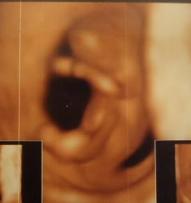

2月20日(11週)

定期健診で4Dを撮影する。

この日初めて赤ちゃんが動いてるのを自分の目で確認できる。

心臓の音(ドップラー音)を聞く。

医学の進歩って凄い。

まだ数cmのはずの赤ちゃんの動きがこんなにはっきり解るなんて。

出血も止まり、安静指示が解除される。